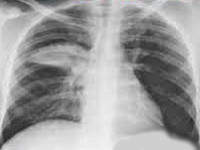

- Рентгенография. При рентгенографии легких выявляется очаговая, сегментарная или долевая инфильтрация либо интерстициальные изменения.